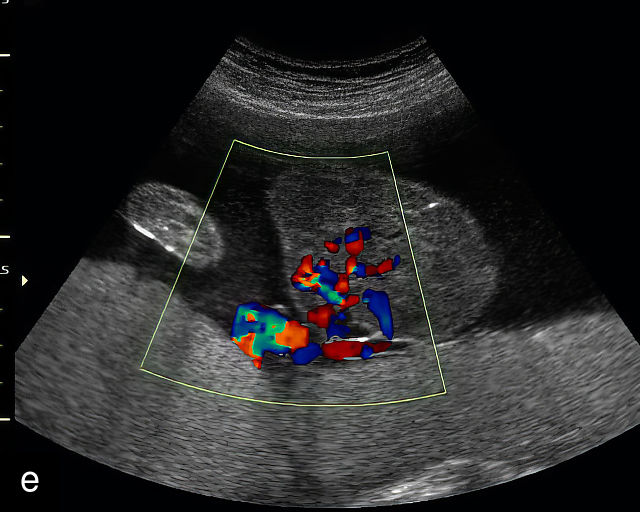

The typical sonographic appearance of a chorioangioma on grayscale ultrasound is a well-circumscribed mass arising from the fetal surface of the placenta, protruding into the amniotic cavity, and distinctly separate from the placenta (Figure 12; Video 7). These tumors are most commonly located near the umbilical cord insertion site on the placenta. Sonographically, they may appear hypoechoic or hyperechoic and are often heterogeneous, with possible calcifications, hemorrhage or infarction visible within the mass.9 The appearance of these masses may change over time.141 Color flow Doppler imaging typically reveals vascularity within the tumor, showing low-resistance vessels and arteriovenous shunts (Figure 12c–e; Video 7).9 These shunts are believed to contribute to fetal complications such as high-output cardiac failure, anemia and hydrops.141 Three-dimensional ultrasound may be helpful in assessment of the mass.146 Importantly, the differential diagnosis includes placental hemorrhage, and color flow Doppler is essential to assist in making the diagnosis.

12

Grayscale (a,b), color Doppler (c,e) and power Doppler (d) images of chorioangiomas, showing heterogeneous masses protruding from the placental surface.

7

(a–c) Color flow and power Doppler imaging of placental chorioangiomas.

When a chorioangioma is identified on prenatal ultrasound, close fetal surveillance is essential. Initial monitoring includes weekly ultrasound examinations to assess amniotic fluid volume and fetal cardiac function, as polyhydramnios and hydrops can develop rapidly. Polyhydramnios is the most common complication of chorioangioma, complicating between 14% and 28% of cases, and when severe, may lead to maternal discomfort, respiratory embarrassment and preterm labor.141,143,147,148 Fetal growth should be evaluated every 4 weeks. Maternal mirror syndrome, with severe pre-eclampsia has also been described.149,150

Management of complications related to chorioangioma may include interventions such as amnioreduction to manage severe polyhydramnios.149,151 More recently, a variety of fetal surgical procedures have been developed to treat these tumors, with varying degrees of success. Additional interventions include intrauterine fetal transfusion to correct anemia and various fetoscopic techniques to occlude tumor vessels, such as embolization with injection of vascular plugs, and radiofrequency or laser ablation of the feeding vessels.143,144,152,153,154,155,156,157